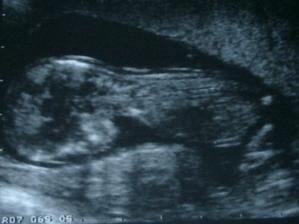

Príbeh Emky alebo Adamka 🙂

Asi budem Adamko, lebo instinktivne to tak mamina silno citi, ale uvidime casom, ci sa zo mna nevykluje Emka ;) ... a vyklul sa predsa Adamko!!! 😉 takze mamca to dobre citila!